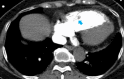

Keywords: POCUS; pulmonary embolism; thrombus in transit.